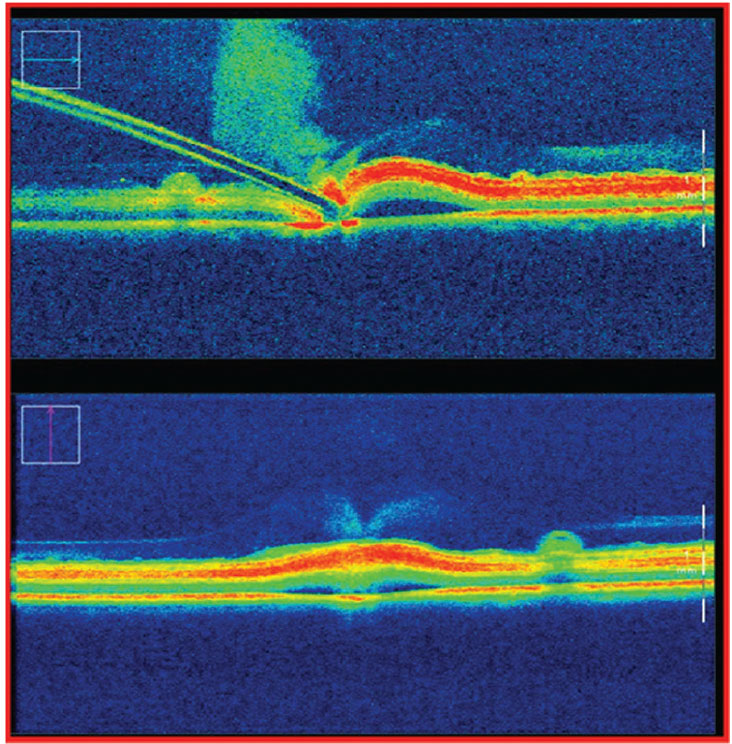

Other non-retinal procedures were also tested, including continuous curvilinear capsulorhexis and lens cortex removal.7 In ex-vivo porcine eyes, the Preceyes platform demonstrated excellent fidelity in subretinal injection procedures when measured with real-time intraoperative optical coherence tomography. It achieved successful bleb creation in 100 percent of eyes using robotic assistance compared with 40 percent using manual delivery. Bleb leakage occurred in all manual cases, compared to only 20 percent of robotic-assisted procedures7 (Figure 2).

Figure 2. Subretinal bleb creation as measured by intraoperative optical coherence tomography during a manual procedure. Of note, on needle retraction, 100 percent of porcine eyes were shown to have efflux of subretinal injection, likely due to surgeon tremor. |